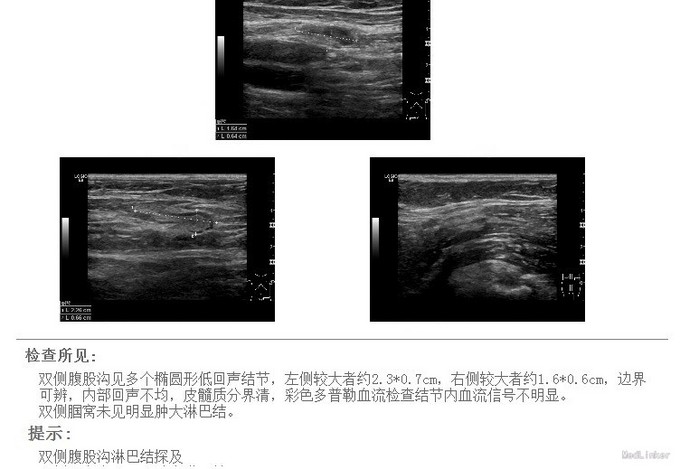

进一步扫全身多处的淋巴结、均有肿大 初步排除cancer,转呼吸内科进一步诊治。 呼吸内科的EBUS-TBNA技术的日趋成熟,对于外科术前分期、判断非常有价值。随着诊疗的个体化呼声越来越高,内、外、病理、影像、放化疗组成的综合肺部肿瘤诊治中心发展前景很大